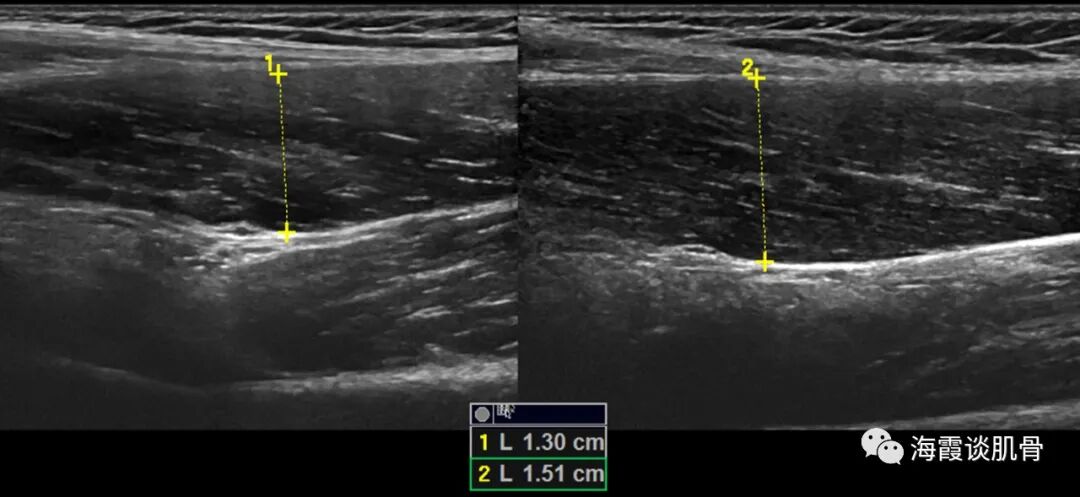

病例1 男,5岁,左侧大腿中部疼痛两天,不敢走路,家长以为生长痛,今病情加重就诊。

图二:左髋关节囊扩张(箭),前隐窝可探及较多液性暗区(箭头),内未见滑膜增生。

图三: 左侧股直肌增厚(15.1mm),形态饱满,回声减低,束状结构模糊,右侧厚约13.0mm,形态回声可。